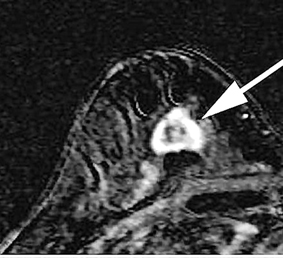

“Bom thông minh” tấn công tế bào ung thư vú